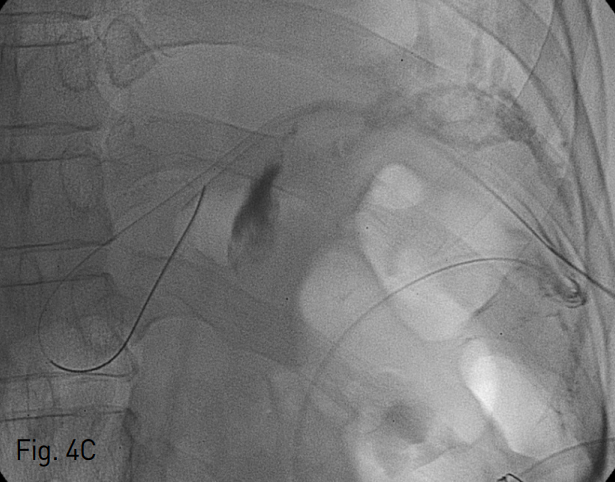

카테터의 U자 모양의 회전부위를 지나면서 피부 아래 공간의 경로가 최단거리이자 직선 경로가 되는 지점을 조준하여 초음파 유도하에 22 gauge Chiba needle로 카테터를 천자하였음 (Fig. 3). 그 후 조심스럽게 바늘을 뒤로 빼면서 hair wire를 초음파와 투시 유도하에 조정하여 바늘이 카테터 바깥 공간에 위치하는 지 확인하였음 (Fig. 4). 이후에 hair wire가 카테터 바깥 공간의 성숙 경로 (maturated tract)를 따라 진입시키고 yellow sheath로 교체하여 조영제를 주입하였을 때 액체 저류가 조영되는 것이 보임 (Fig. 5). 0.035 inch hydrophilic guidewire를 진입시킨 후 8.5 Fr multi-sidehole biliary drainage catheter (Cook, Bloomington, IN, USA)를 거치하였음 (Fig. 6). 이후 50cc 정도의 냄새가 나는 연노란색의 농이 배액되어, 카테터를 배액용기에 연결한 후 시술을 종료함.

Fig. 4

Ultrasonography and fluoroscopy guided 22 gauge Chiba needle is inserted in to the Jackson Pratt drainage catheter induced maturation tract directly on anteroposterior (A) and right 45 degree oblique (B) fluor oscopy images. Hair wire in the Jack son-Pratt drainage catheter induced matur ation tract on fluoroscopic image (C).